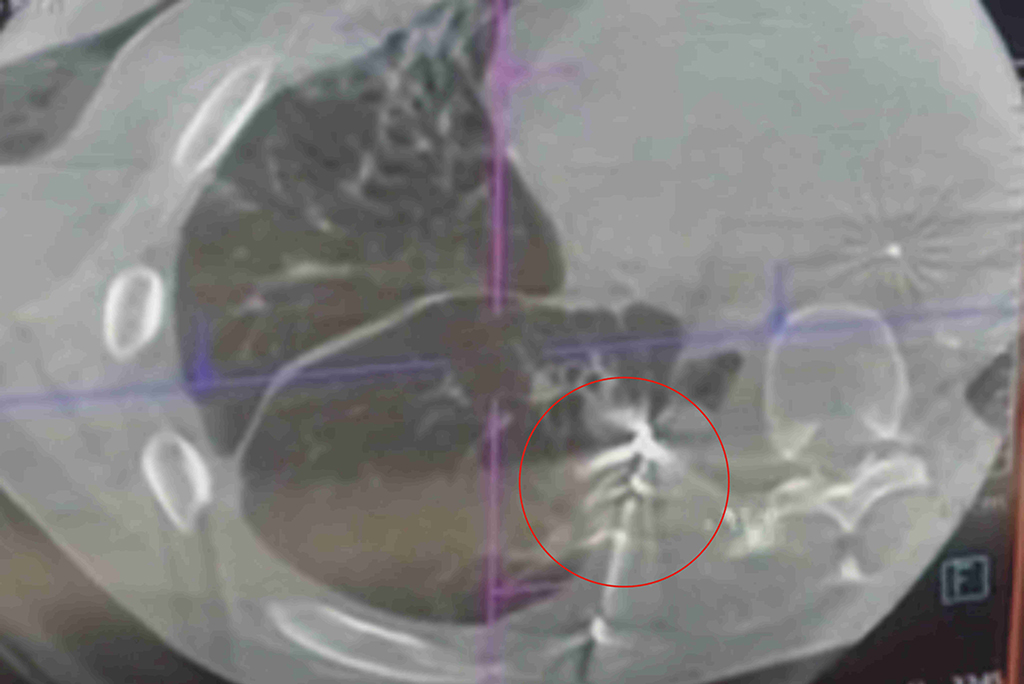

鄭雅夫醫師指出,一位52歲男性為因為罹患下咽癌合併多處轉移,經過化療及免疫治療後,仍然有右上肺及右下肺的腫瘤存在。患者於7個月前接受胸腔鏡右上肺及右下肺部分切除後腫瘤控制較穩定。此次再次發現右下肺長出一顆三公分的腫瘤,有鑑於病患的肺功能不佳,二次手術也容易沾黏較不合適,於是選擇了在複合式手術室中做微波肺部消融術治療,術後腫瘤消融狀況良好,病患也於觀察一天後即可出院,肺部消融術是一項針對不適合接受肺部切除術的良好替代選擇。

52歲男性患者,微波消融術前,右下肺一顆3公分腫瘤。

52歲男性患者,腫瘤經微波消融術而壞死。